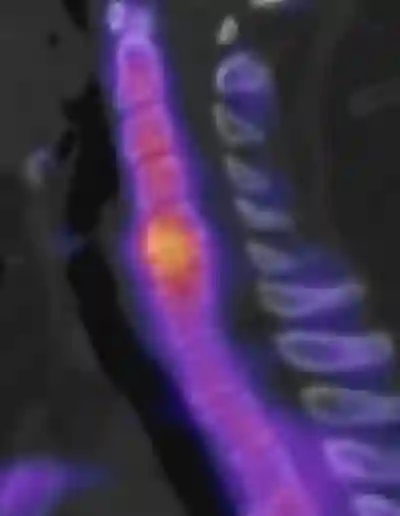

SPECT/CT Wirbelsäule

Sagittales SPECT/CT mit Darstellung von aktiven Osteochondrosen auf Höhe LWK3/4 und LWK2/3.